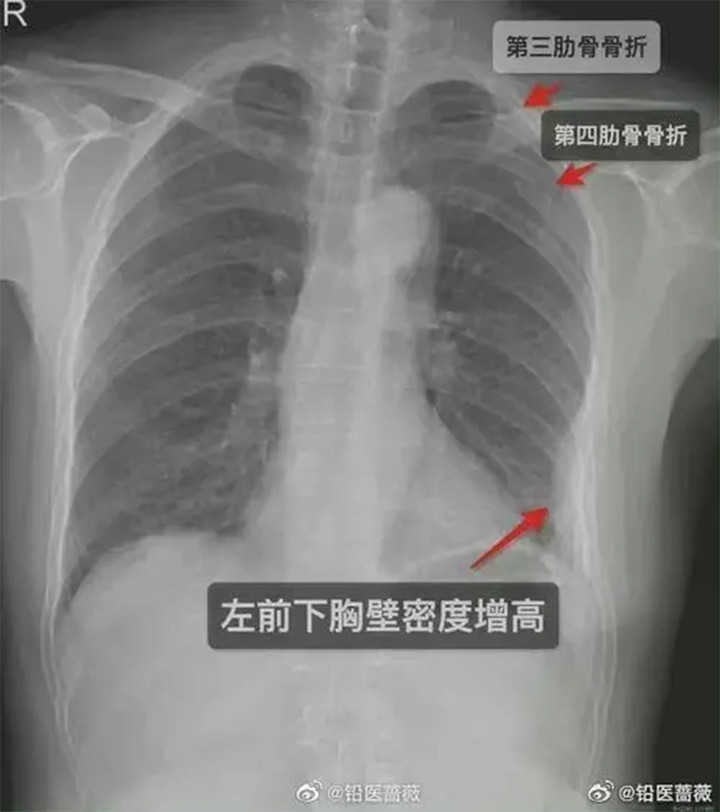

Phim X-quang của cô gái cho thấy có 3 cái xương sườn bị gãy.

Tòa kết luận rằng cái ôm của nam đồng nghiệp đã khiến cho cô gái bị gãy 3 cái xương sườn, do đó anh ta phải bồi thường 10.000 tệ (gần 35 triệu đồng). Dù thương tích của cô được phát hiện sau cái ôm 5 ngày, tòa cho rằng không có chứng cứ nào chứng minh trong 5 ngày đó, cô gái có những hành động hay gặp sự cố gì dẫn đến gãy xương sườn. Hơn thế, những đồng nghiệp khác cũng đã làm chứng rằng cô gái tỏ ra đau đớn và hét lên khi bị ôm.